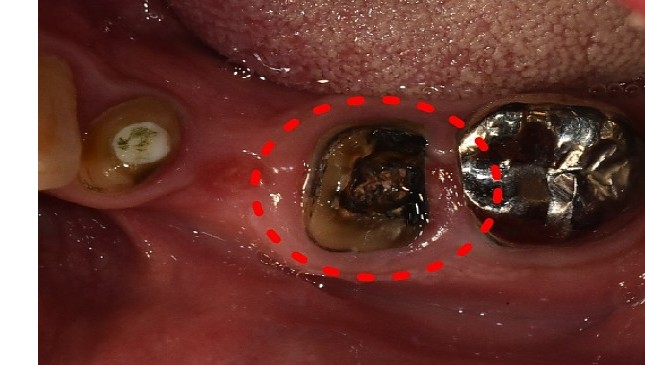

치아살리기 치료 전후 사진

잇몸 전체가 무너져 동시다발적으로 죽어가던 치아들을 한꺼번에 살려 냅니다.